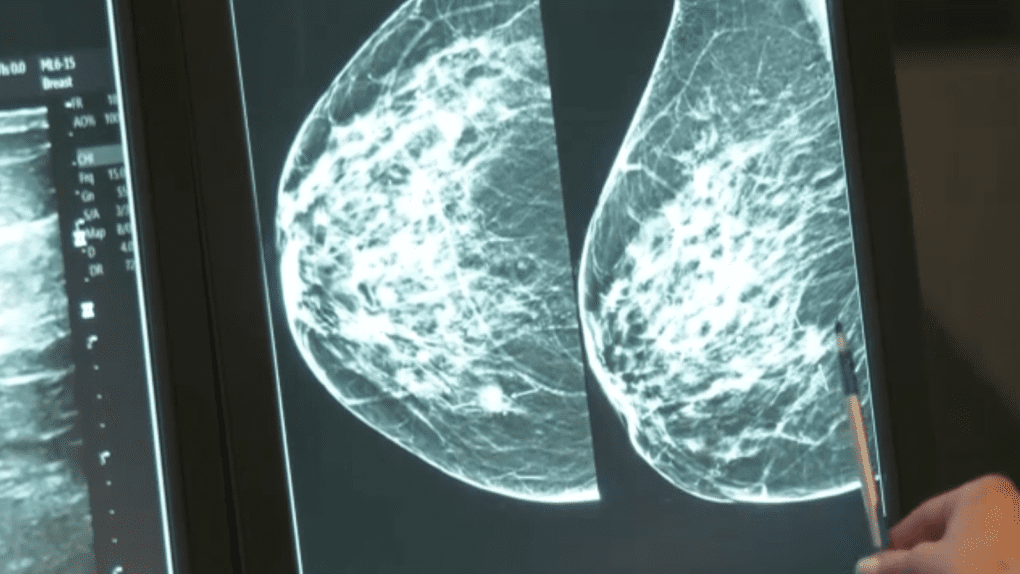

Как в Ванкувере делают маммографию и что чувствует женщина во время процедуры?

Женщина встает перед специальным рентгеновским аппаратом. Технолог кладет грудь на одну пластину, вторая будет плотно прижимать молочную железу сверху. Пластины расплющивают грудь, удерживая ее во время рентгеновского снимка. Человек в течение процедуры может испытывать не очень приятное давление, но в целом процесс не вызывает сильного дискомфорта. Обычно делают два снимка, чтобы врач мог посмотреть на грудь со стороны. Другая молочная железа будет обследована таким же способом. Затем женщина ждет в кабинете пока технолог проверит рентгеновские снимки, чтобы убедиться, что их не нужно переделывать. Также следует отметить, что технолог не имеет права сообщать о результатах маммографии, это должен сделать квалифицированный врач.

Проходить маммографию для большинства девушек неудобно, некоторым женщинам даже больно, однако это обычно связано с проблемами со здоровьем. Однако маммография длится всего несколько минут, что не может не радовать пациенток. Кроме того, стоит знать, что ощущения во время процедуры зависят от квалификации технолога (в Ванкувере с этим проблем нет), размера груди и того, насколько их нужно прижать. К тому же у кого-то молочные железы более чувствительны, например, если вскоре у женщины менструация. Врач, имеющий специальную подготовку, называется радиологом, в Ванкувере он сразу проверит рентгеновский снимок на наличие ранних признаков рака молочной железы или других проблем.

В Ванкувере советуют проходить маммографию в соответствии с рекомендованными интервалами времени. Ведь маммографии работают лучше всего, когда их можно сравнить с предыдущими. Это позволяет рентгенологу сопоставить их, чтобы выявить изменения молочных желез пациенток. Также стоит отметить, что маммограмма каждой женщины может выглядеть несколько по-разному, потому что вся грудь уникальна.